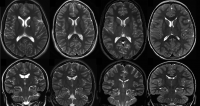

In this study, geneticists sequenced DNA from brain tissue and blood samples of 56 individuals with intractable neocortical epilepsy, a type of epilepsy that doesn’t respond well to any anti-seizure medication. Nearly 9 percent of the study participants were found to have a subset of their brain cells with a small genetic difference in the gene SCL35A2 that was not detectable in the blood and very likely responsible for the seizures.